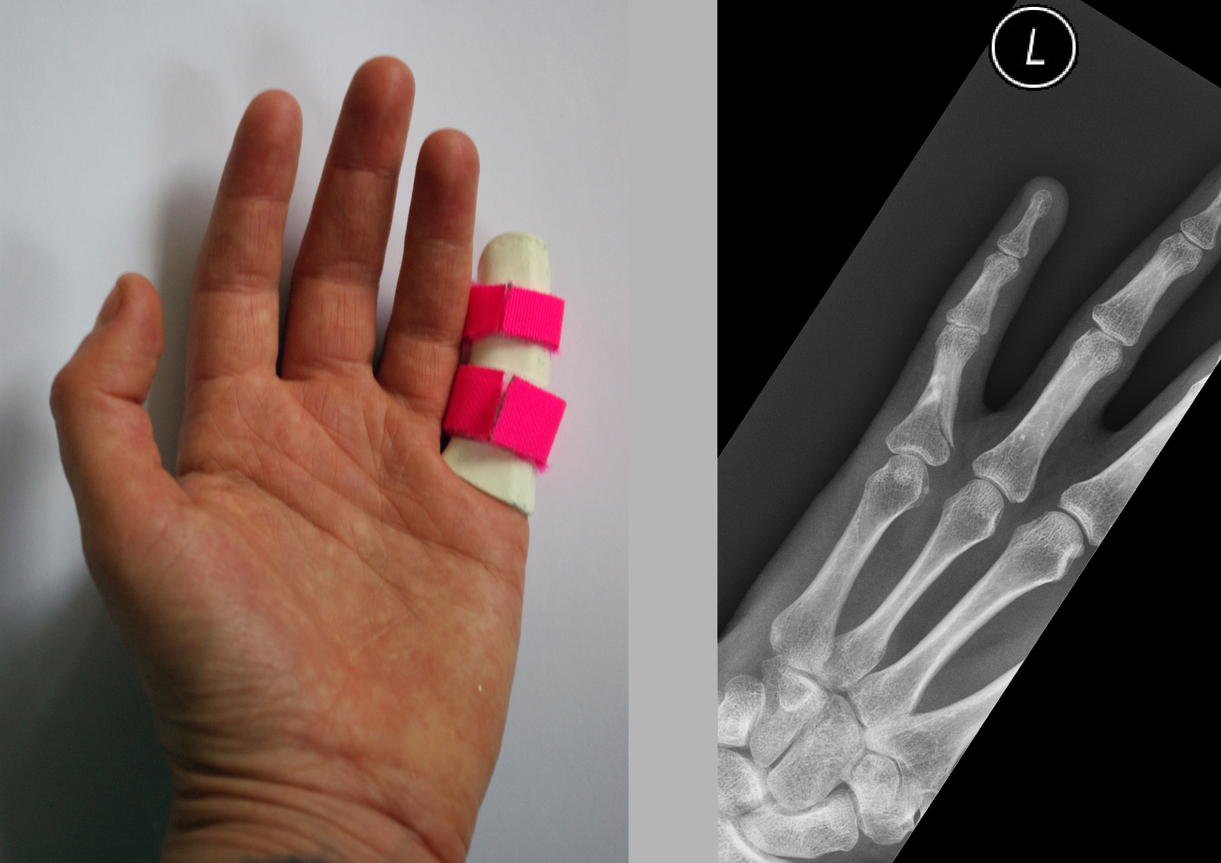

When my arm was in plaster I initially found that the plaster felt supporting because it restricted movement which had been painful. It took over the job on the outside that the bone would have done on the inside, forming an exoskeleton, and by doing so gave the bone the opportunity to heal itself. By the second week the pain had died down and I wanted to be able to move my wrist and thumb but couldn’t. As well as being supported I now felt contained in the plaster; restricted and uncomfortable. After six weeks of not moving my hand it began to ache and I really felt the restriction of not being able to clench my fist. The bones in the hand move in so many directions all of which had been immobilised in the plaster except wiggling my fingers to keep circulation. When the plaster was taken off after nine weeks my hand was rigid and completely immobile, my wrist was locked solid and all my muscles had completely wasted away leaving a bony, shrivelled, scaly, distorted object. I had been looking forward to being able to move it again but the combination of being so stiff and feeling so fragile meant that much of the restriction remained even after the plaster was removed.

Whether the cast on my arm felt supportive or restricting was dependant on the condition of the arm. When the wrist was most injured and needed support then it was a positive experience. Once healed well enough the plaster served as protection from knocks for the new soft bone but also became restrictive. Whilst the plaster supports the bones it also causes the muscle to waste and this creates a conflict between doctors and physiotherapists. The doctor is concerned with the bone rather than the movement and so can be tempted to leave the plaster on too long causing irreversible damage to movement. There is a fine line between providing support and causing damage through restriction. What I find interesting in the tension between the physiotherapist and doctors is that the latter seeks to secure a static structure in repairing the bone whereas the physiotherapist’s purpose is to help restore movement in freeing the joints and rebuilding muscle.